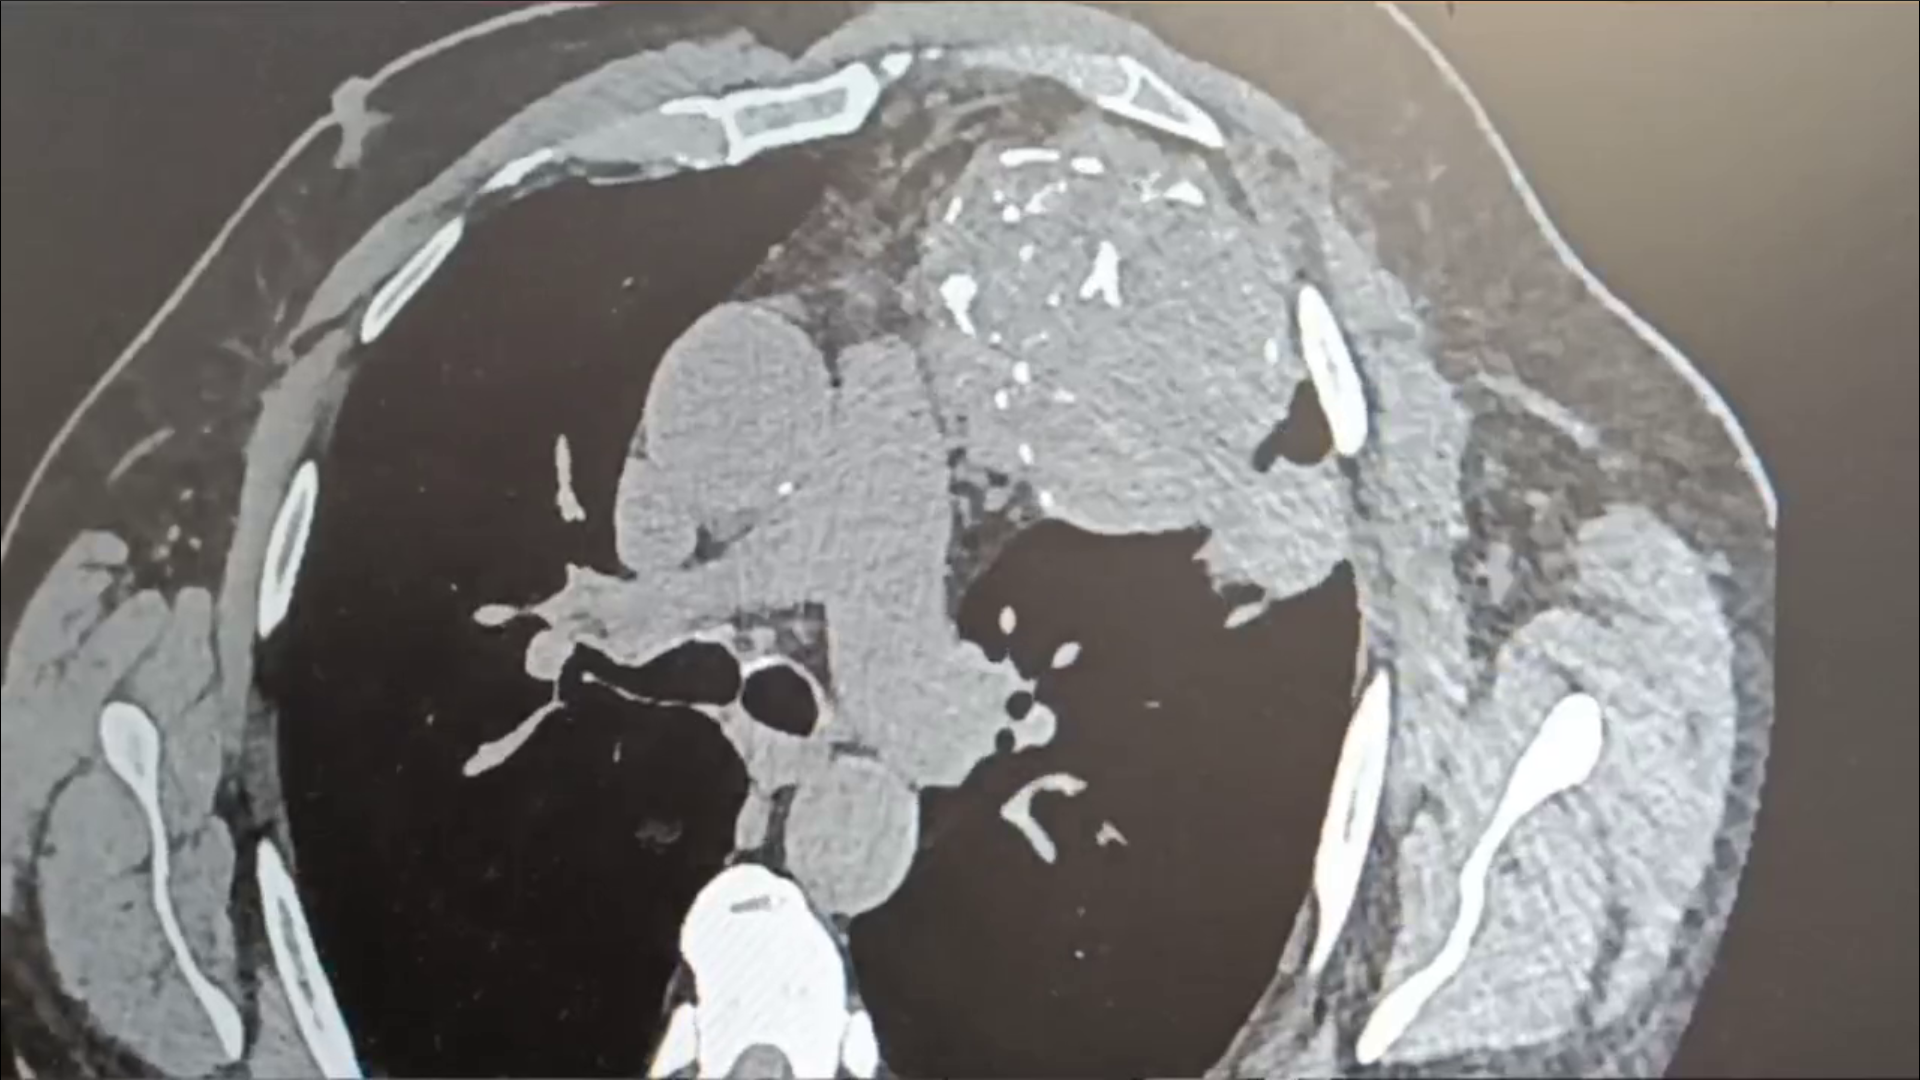

Торакальные хирурги Оренбургской ОКБ №2 провели сложную операцию. У жителя Орска они удалили огромное новообразование в грудной клетке.

Опухоль появилась 20 лет назад – между сердцем, правым легким и ребрами. Первоначально новообразование не мешало орчанину. Но постепенно сильно разрослось и дало знать приняв большие размеры.

Обострение произошло недавно, в период пневмонии у пациента. Опухоль начала сдавливать легкое. Находясь на лечении в ООКБ №2, мужчине предложили удалить опухоль.

— Операция длилась почти 3 часа. Работу хирургов осложняло близость новообразования к крупнейшим кровеносным сосудам и сердцу. Наши опытные специалисты справились с этой ситуацией, аккуратно удалили опухоль не задев жизненно важных сосудов и органов, — сообщили в региональном минздраве.